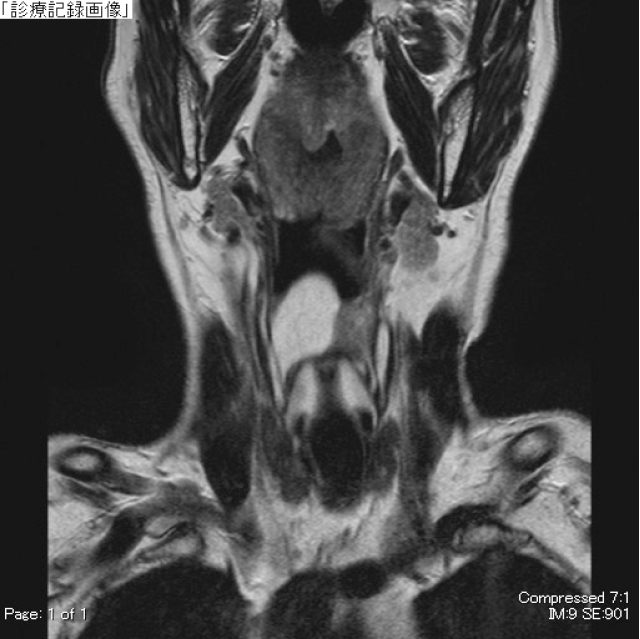

頸部MRI:右梨状窩付近に境界明瞭な24mm大の腫瘤を認める.腫瘤はT1及びT2強調画像で高信号(Figure 3,4),脂肪抑制T1強調画像で低信号を呈し(Figure 5),著明な拡散異常や内部造影効果は認めなかった.

MRI T2強調,冠状断像.腫瘤は境界明瞭で高信号を呈する.